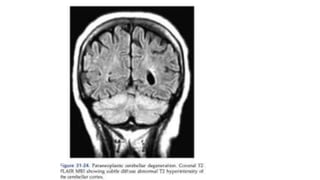

• MRI: limbic encephalitis because medial temporal lobe show increased FLAIR

• Paraneoplastic cerebellar degeneration may develop atrophy significant on MRI

Other diagnostics • Canbe difficult when antibodies not detected • Absence of ab does not exclude paraneoplastic syndrome • Several diagnostic tests are helpful: • MRI: limbic encephalitis because medial temporal lobe show increased FLAIR • Paraneoplastic cerebellar degeneration may develop atrophy significant on MRI • PET: fluorodeoxyglucose will occasionally identify hypermetabolism of medial temporal lobe with limbic encephalopathy • LP: detection of AB confirms diagnosis, anti-Tr antibodies and patients with antibodies to antigen expressed in the cell membrane of neurons of the neuropil of hippocampus ANTI NMDA receptor titres in the CSF but not serum • Electrophysiology: LEMS, myasthenia gravis, neuromyotonia, dermatomyositis • Cancer search: Lung with LEMS, thymus with MG